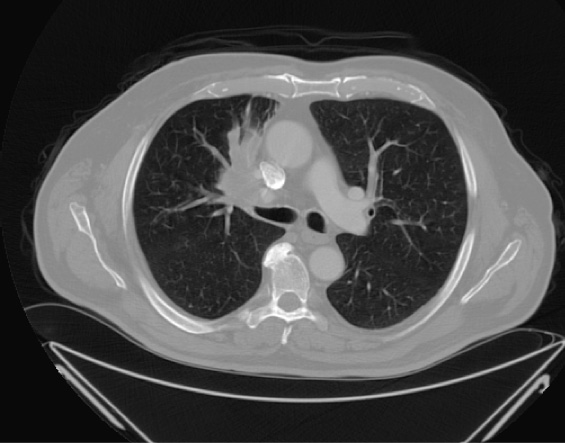

Figura 1. Valutazione strumentale alla diagnosi con TC del torace con mezzo di contrasto: neoformazione in sede peri-ilare destra sospetta per lesione eteroproduttiva

Il paziente, su indicazione dello stesso ortopedico, esegue una visita pneumologica, durante la quale viene posta indicazione a eseguire tomografia computerizzata (TC) del torace con mezzo di contrasto, che evidenzia una lesione in sede peri-ilare destra di circa 65 × 50 mm, a margini irregolari, intrascissurale, di sospetta natura evolutiva, con adenopatie di diametro moderatamente incrementato in sede ilare, paratracheale destra e sottocarenale (diametro compreso tra 12 e 20 mm) sospette per coinvolgimento neoplastico (Figura 1).